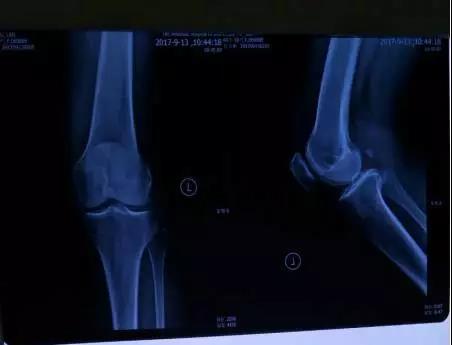

ÔÚ¼ÒÈ˵ÄÅãͬÏ£¬³ÂÒÌÂèÈ¥ôßÄÏ´óѧÁ¥ÊôµÚÒ»Ò½Ôº×ö¼ì²éÏÔʾ£º 1.Ï¥ÊàŦÇá¶ÈÍËÐÐÐԸı䣻2.Íâ²à°ëÔ°åǰ½Ç¼°ÄÚ²à°ëÔ°åºó½Ç±äÐÔ£»3.÷ÆÉÏ»¬Ä¤ÄÒ¼°ÊàŦÄÒÉÙÁ¿»ýÒº¡£Ò½Éú¿ªÁËЩÏûÑ×ֹʹµÄÒ©ÎÖÎÁÆÐ§¹û²»ÏÔ×Å£¬ØÊºó×Ô¼ºÓÖÕÒÅóÙ¿ªÁËЩÖÐÒ©£¬Ò²ÊÇЧ¹ûÉõ΢¡£ÔÆÔÆÖظ´£¬ÕÛÌÚÁËÒ»¸öÔ£¬Ï¥ÊàŦÌÛʹʼÖÕûÓлñµÃ¸ÄÉÆ¡£ØÊºóÔÚÅóÙµÄÏÈÈÝÏ£¬À´µ½ôßÄÏ´óѧ¡°×ðÁú¿Ê±ÊÖÒÕ¡±ÖÎÁÆÊÒ¡£×îÏȽÓÊÜ¡°×ðÁú¿Ê±ÊÖÒÕ¡±ÖÎÁÆ¡£